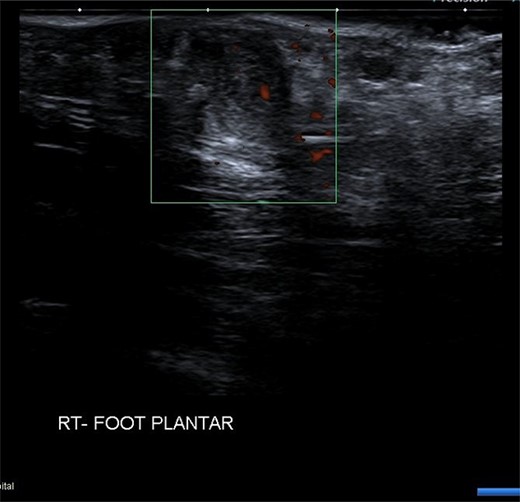

USS described this swelling in the plantar aspect of the midfoot as a well-defined, hypoechoic tender lesion within the plantar subcutaneous tissue measuring ~17 × 7 × 11 mm. More importantly, the lesion extended deep to the plantar fascia not arising from it, hence ruling out plantar fibromatosis (Fig. 1). In order to rule out any aggressive pathology, a magnetic resonance imaging (MRI) with contrast was arranged, which revealed a 2 cm by 5 mm tubular oblique lesion in the plantar subcutaneous fat. MR imaging was also able to rule out sinus tarsi syndrome and any internal derangements (Figs 2 and 3). She was referred to Orthotics for a medial support arch to help with pain. Since the exact characteristics of this lesion were still unknown, the case was referred to the Yorkshire Sarcoma Multi-disciplinary team (MDT). The outcome of this meeting concluded that there were no radiological features of a sarcoma. She still experienced an excruciating, sharp stabbing pain in her right foot. Pain score was 10/10. She opted for the surgical excision biopsy of the lesion. The post-operative period was uneventful with good healing of the wound. She was followed up 2 months, and with the histology findings, results revealed a rare soft tissue neural neoplasm in keeping of a neurofibrolipoma. The patient was happy with the overall outcome and was discharged. She was reviewed again after 2 years for a further foot and ankle problem in the other foot, and at the time of review, she was completely pain-free in the right foot with an excellent outcome.